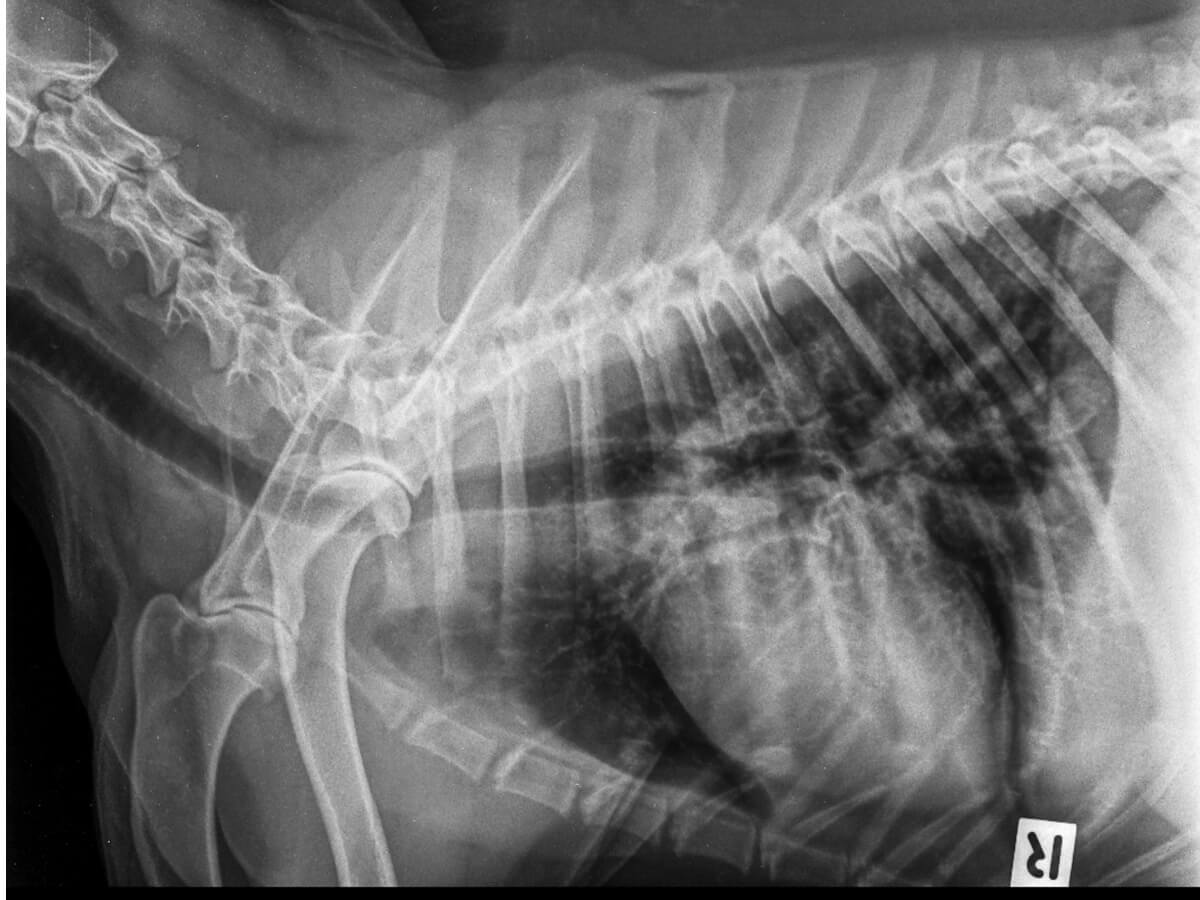

Plaques radiographiques

L’utilisation de la radiologie permet d’observer la présence d’air au-delà des poumons. Elle est considérée comme un test précis pour le diagnostic du pneumothorax chez le chien, mais pas pour en identifier la cause.

Il est recommandé de réaliser trois projections, car cela permettra de visualiser toutes les anomalies des structures au sein de la cavité thoracique. La manipulation doit être délicate pour éviter d’augmenter le stress de l’animal.